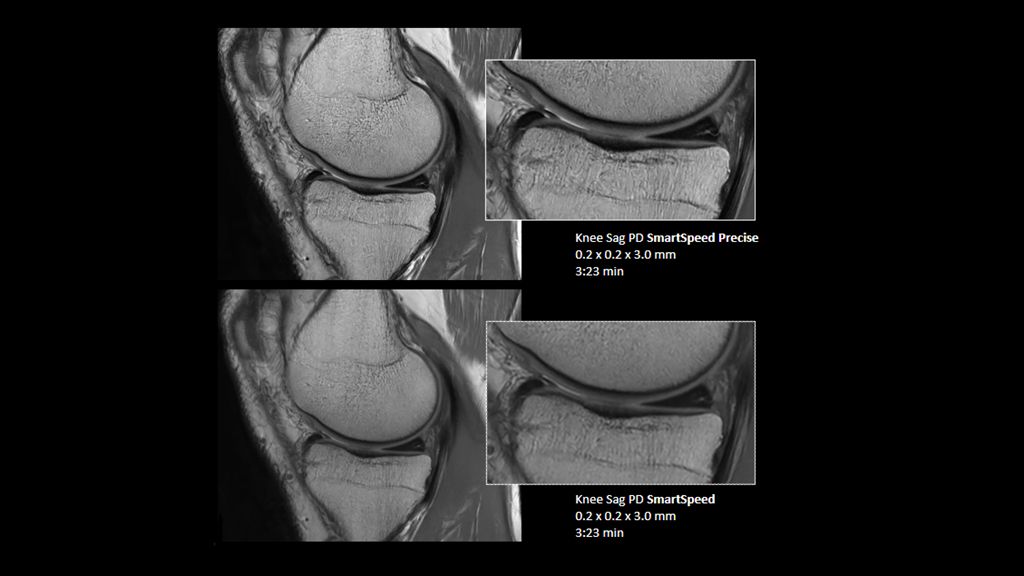

2. Reconstruction technology Compared to conventional (SENSE/ Compressed SENSE, SmartSpeed AI) imaging. Sharpness was evaluated with phantom scanning.